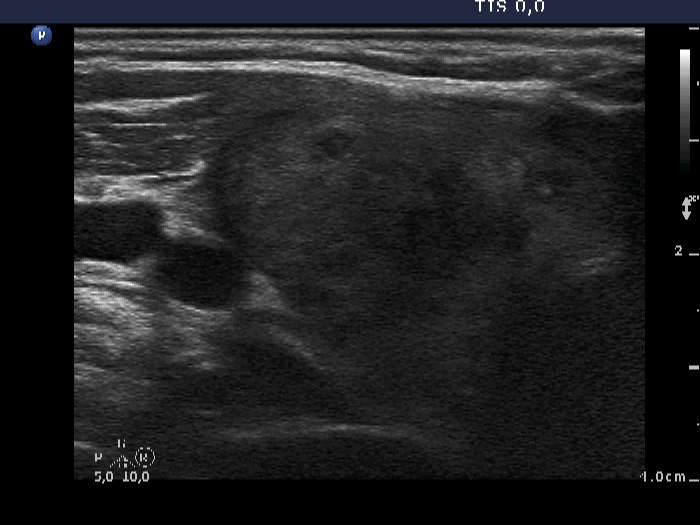

Initial examination (1st and 2nd rows of images):

Clinical presentation: a 50-year-old woman was referred for an evaluation of neck pain localized to the right thyroid and fever.

Palpation: the right thyroid was painful and hard.

Laboratory examination: hyperthyroidism (TSH 0.01 mIU/L, FT4 43.4 pM/L), CRP 18.3 mg/L.

Ultrasonography: there were multiple hypoechogenic areas with ill-defined borders in both lobes, primarily in the right one. The vascularization was decreased.